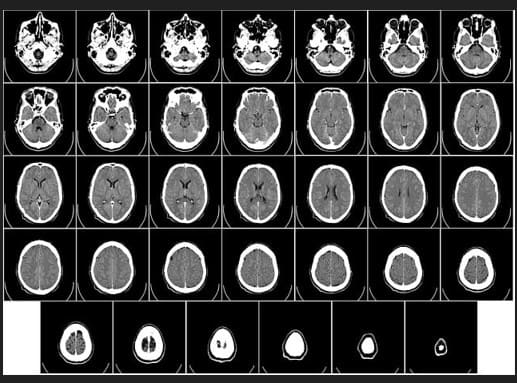

✅ MRI 검사란?

MRI(Magnetic Resonance Imaging)는 강한 자기장과 고주파를 이용해 인체 조직의 수소 원자 반응을 영상화하는 기술입니다.

연부조직, 신경, 인대, 연골 등 미세한 구조를 매우 정밀하게 확인할 수 있어 디스크, 뇌질환, 암 등에서 필수 검사입니다.

🧠 MRI 주요 활용 예

- 뇌졸중, 뇌종양, 다발성 경화증 진단

- 허리디스크, 척추 협착증, 관절 연골 손상

- 자궁근종, 난소 종양, 전립선 질환